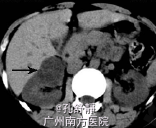

入院后查血肌酐为158umol/L,移植肾功能良好。腹部CT提示右肾巨大占位性病变,且分隔,考虑右肾肾癌。

诊断:右肾占位性病变,考虑右肾肾癌 处理:检查提示肾癌可能性大,跟患者和患者家属讨论后决定手术治疗,于是在入院后第3天在我院行右侧肾癌根治术,术后取活检确诊为肾癌,术后结合化疗。